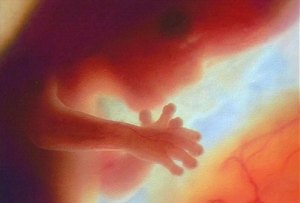

Fetus at 20 Weeks

All pictures came from:  http://www.webmd.com/baby/slideshow-fetal-development